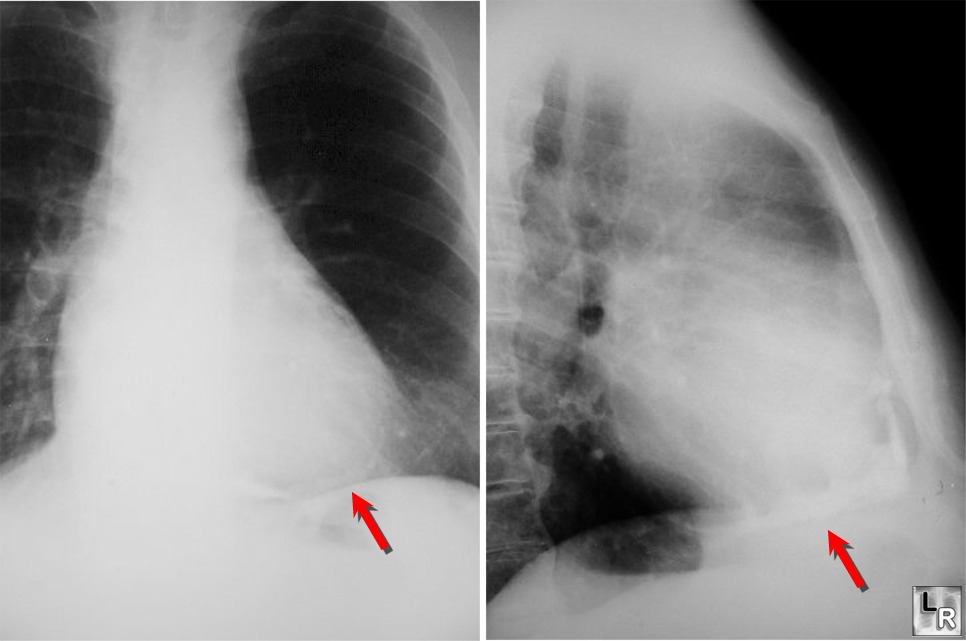

Η περικαρδίτιδα που προκαλείται από φυματίωση

Η φυματιώδης περικαρδίτιδα, ICD-10-CM A18.84 ή φυματίωση του περικαρδίου, προκαλείται από άμεση επέκταση από μεσοθωρακικούς φυματιώδεις λεμφαδένες ή λόγω αιματογενούς διασποράς.

Χαρακτηρίζεται από περικαρδιακό ήχο τριβής, περικαρδιακή διήθηση, πυρετό, ταχυκαρδία, θωρακικό άλγος και ταχύπνοια.